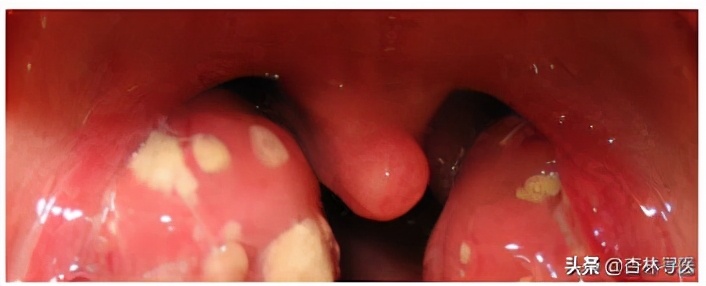

扁桃体上渗出化脓图片来源网络

造成儿童成人咽痛可能的原因很多,除了细菌,绝大多数是病毒,其次还有非感染性因素,比如环境因素等。A组链球菌(Group A Streptococcus, GAS),是儿童和青少年细菌性咽炎最常见的病原体。这个细菌平常是可以无症状定植在我们的咽喉中,据报告,健康成人的带菌率为4%-5%,儿童为2%-20%。带菌状态可持续数月至数年。这些感染状态中,只有症状性链球菌感染才需治疗。我们在5-15岁儿童中,15%-30%的急性咽炎是由A组链球菌引起,孩子除了咽痛可能伴发热、头痛、腹痛、恶心及呕吐,因为嗓子疼可能会拒绝进食加上发热使用退热药后大量出汗可能导致脱水。其他特征可能包括:扁桃体上化脓,像白色的斑片,所以俗称化脓性扁桃体炎,扁桃体红肿、颈前淋巴结肿大压痛、腭部瘀点和悬雍垂发炎,以及猩红热样皮疹(红色斑点,按压变白,小的高出皮肤表面的突起,摸上去像砂纸一样,皮疹消退时蜕皮)。